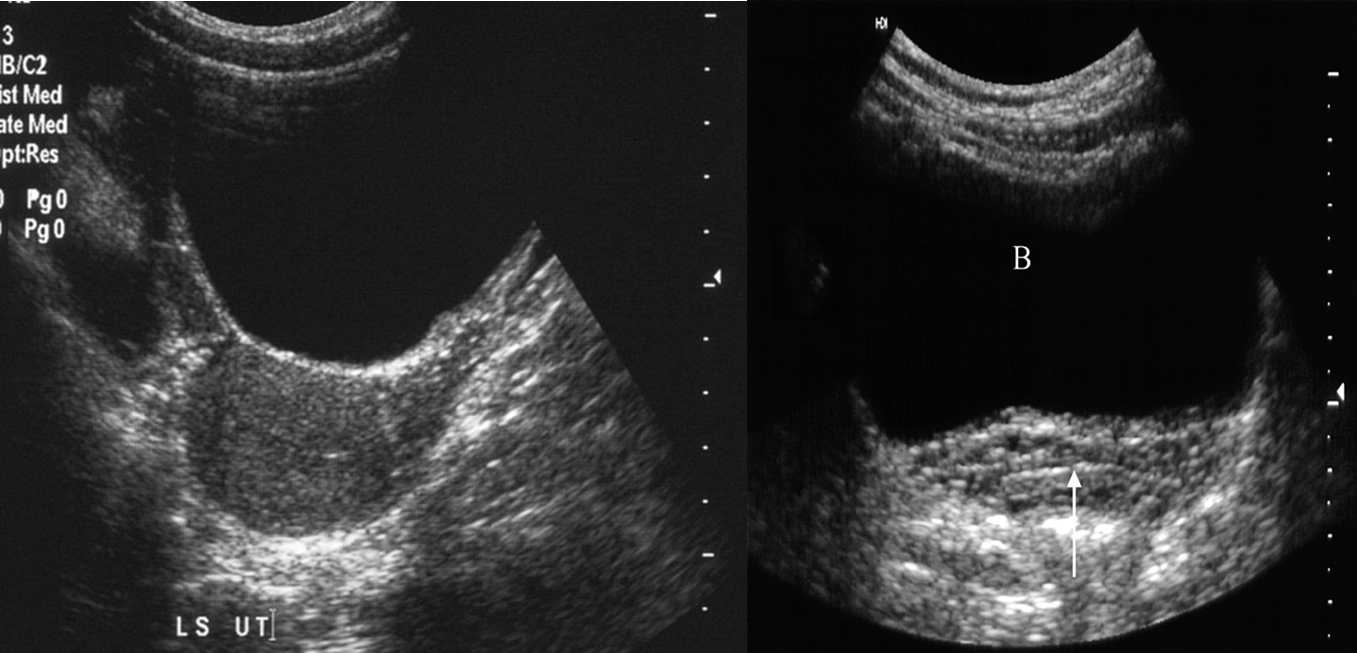

The urinary bladder should be examined in the distended state: the walls should be sharply defined and barely perceptible.

Female

Normal ultrasound of the full bladder (B). Note the smooth thin bladder wall. The vagina lies posteriorly (arrow).